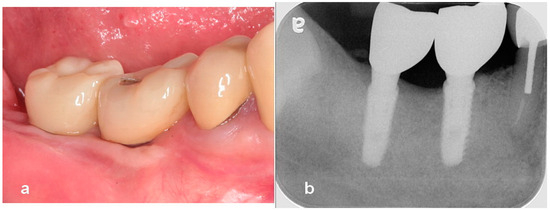

Utilization of Tenting Pole Abutments for the Reconstruction of Severely Resorbed Alveolar Bone: Technical Considerations and Case Series Reports

2. Case Presentations

- Woo, R.H.; Kim, H.G.; Kim, G.; Park, W.E.; Sohn, D.S. Simplified 3-dimensional ridge augmentation using a tenting abutment. Adv. Dent. Oral. Health 2020, 12, 185–205. [Google Scholar]

- Sohn, D.S. Reconstruction of three-dimensional alveolar ridge defects utilizing screws and implant abutments for the tent-pole grafting’ techniques. In Essential Techniques of Alveolar Bone Augmentation in Implant Dentistry, 2nd ed.; Tolstunov, L., Ed.; Wiley Blackwell: Hoboken, NJ, USA, 2023; pp. 404–418. [Google Scholar]